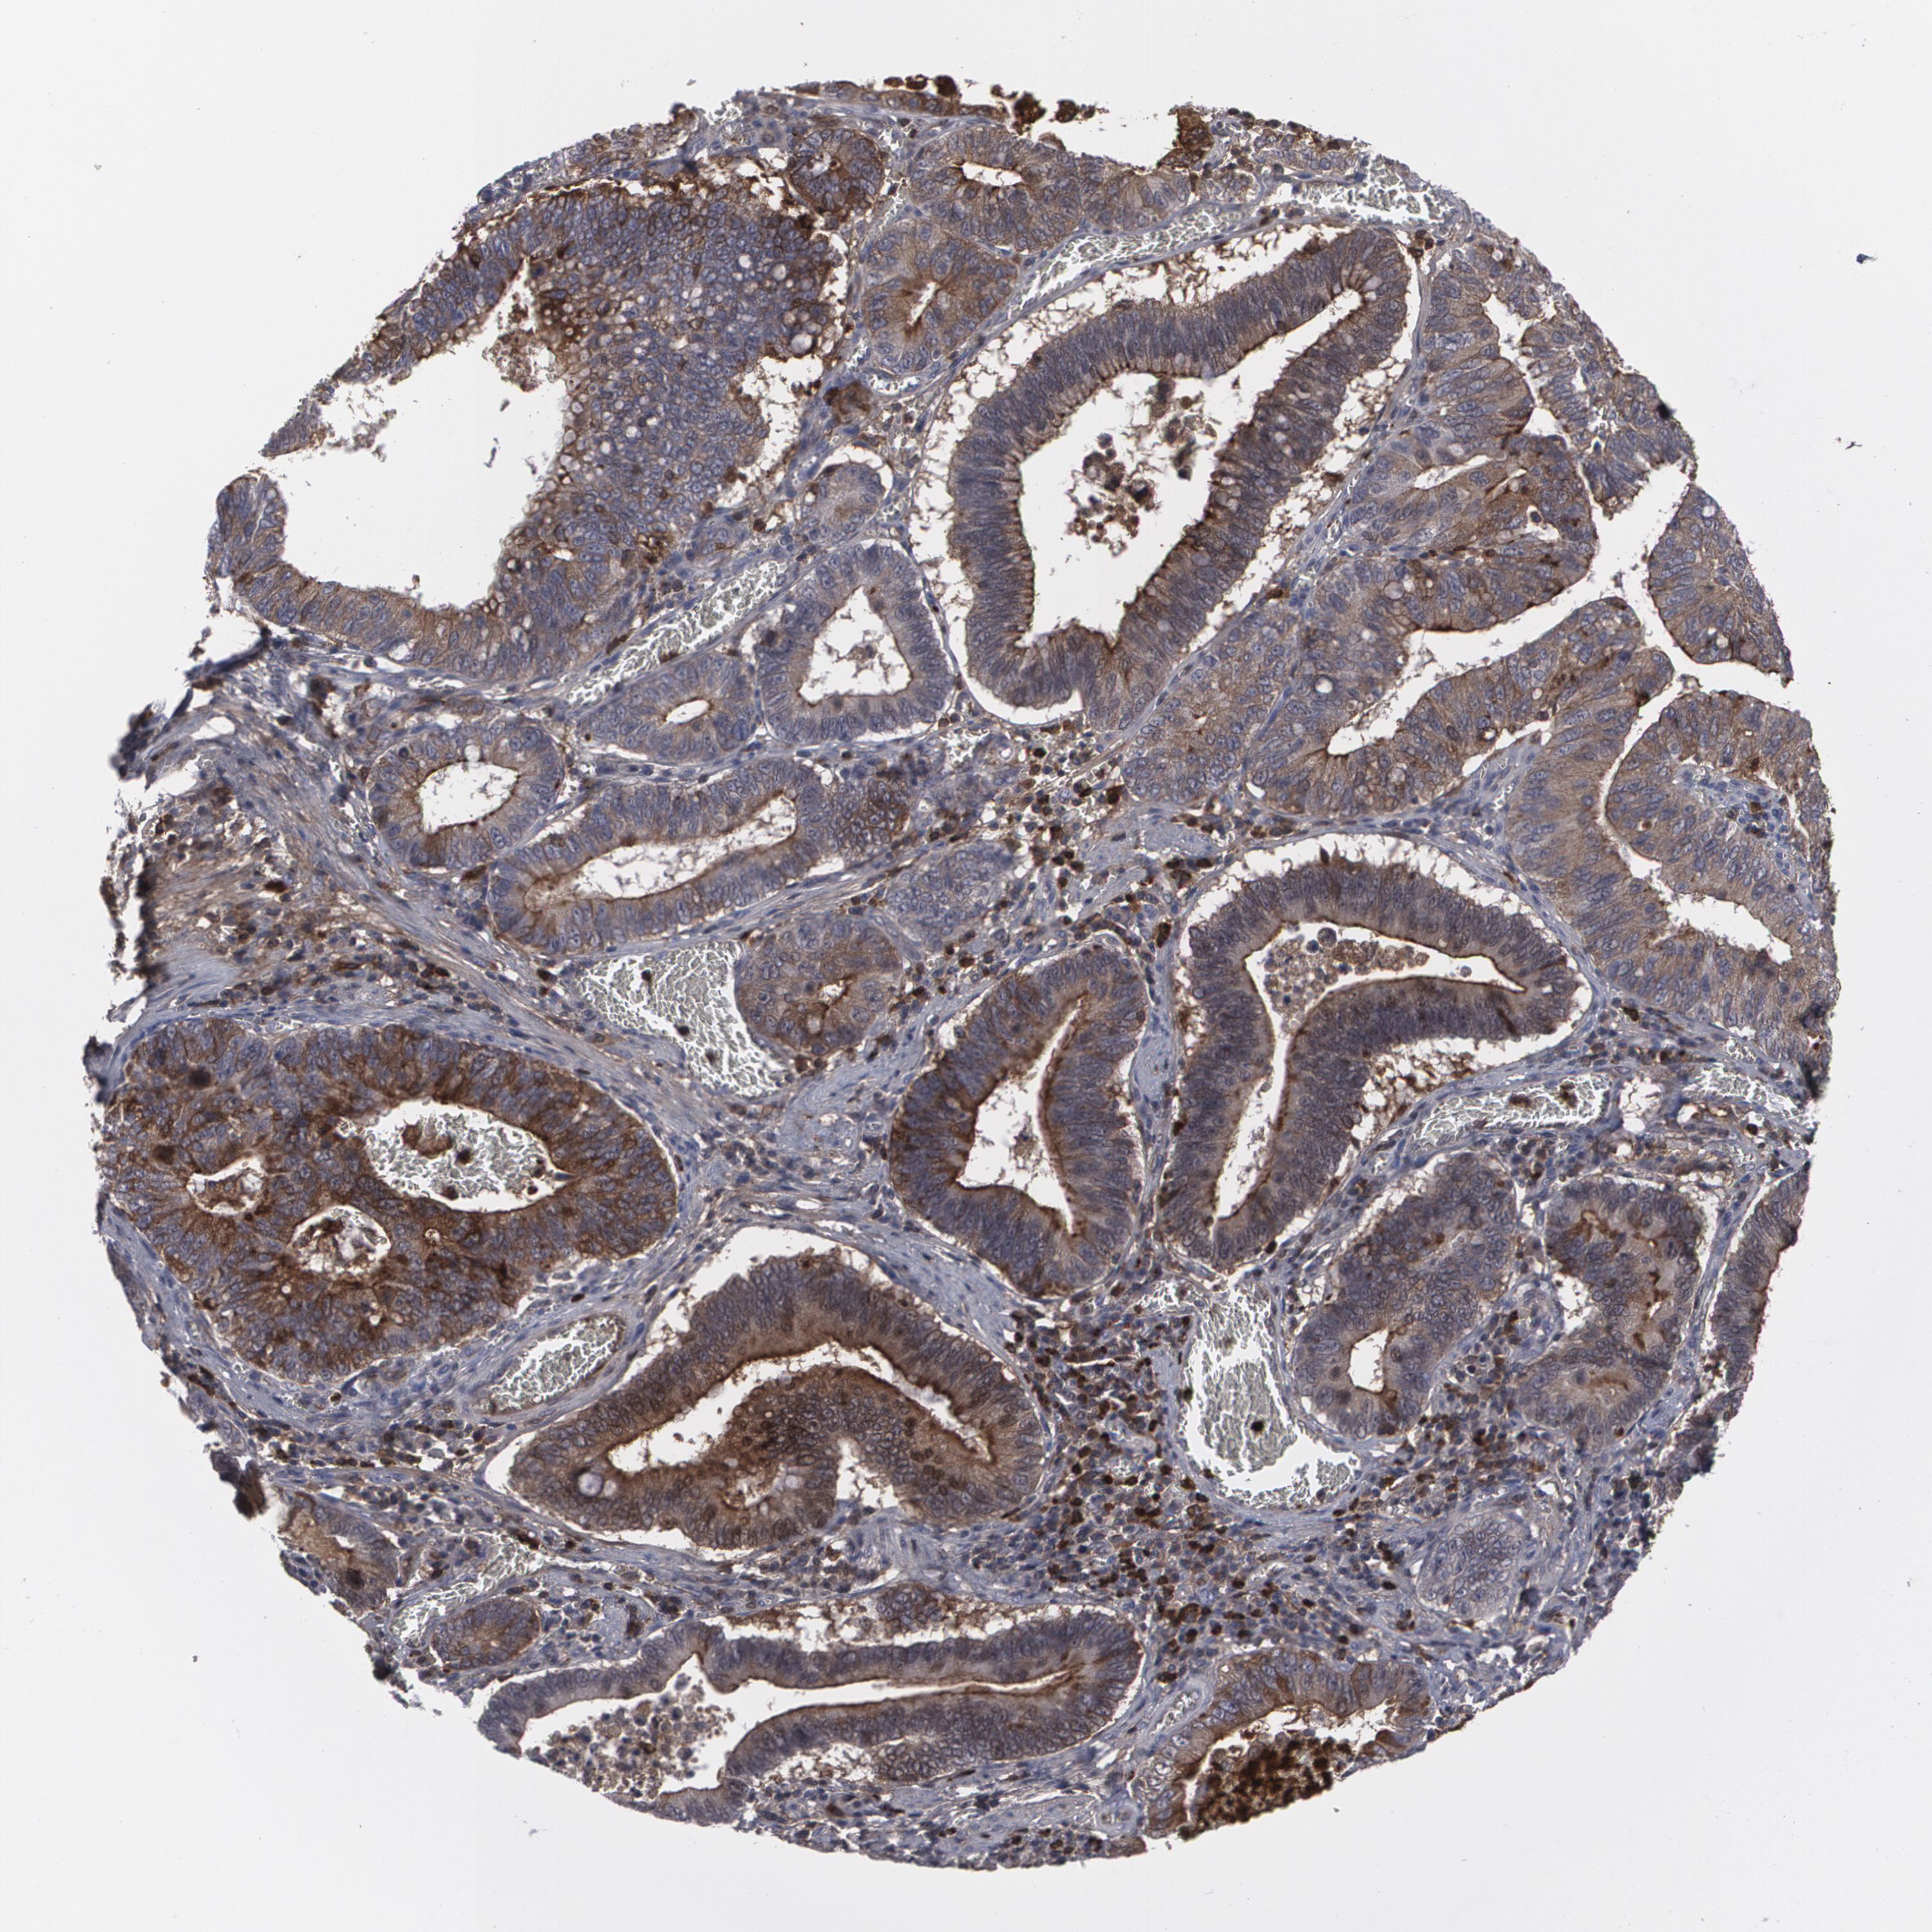

STOMACH CANCER - Protein expressioni

A mouse-over function shows sample information and annotation data. Click on an image to view it in a full screen mode. Samples can be filtered based on level of antibody staining by selecting one or several of the following categories: high, medium, low and not detected. The assay and annotation is described here.

Note that samples used for immunohistochemistry by the Human Protein Atlas do not correspond to samples in the TCGA dataset.

Antibody stainingi

Antibody staining in the annotated cell types in the current human tissue is reported as not detected, low, medium, or high, based on conventional immunohistochemistry profiling in selected tissues. This score is based on the combination of the staining intensity and fraction of stained cells.

Each image is clickable and will lead to virtual microscopy that enables deeper exploration of all samples and also displays staining intensity scores, fraction scores and subcellular localization as well as patient and tissue information for each sample.

Antibody HPA001888

Antibody HPA001889

Staining

High

Medium

Low

Not detected

Intensity

Strong

Moderate

Weak

Negative

Quantity

>75%

75%-25%

<25%

None

Location

Nuclear

Cytoplasmic/membranous

Cytoplasmic/membranous,nuclear

Adenocarcinoma, NOS

Adenocarcinoma, High grade